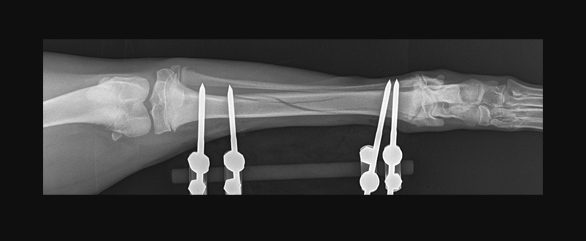

Fixator surgery

Fixators, both linear (straight) and circular may also be used to temporarily stabilise the bone whilst healing, and these are visible externally (external fixators).

Drag the circle to view before and after surgery images.